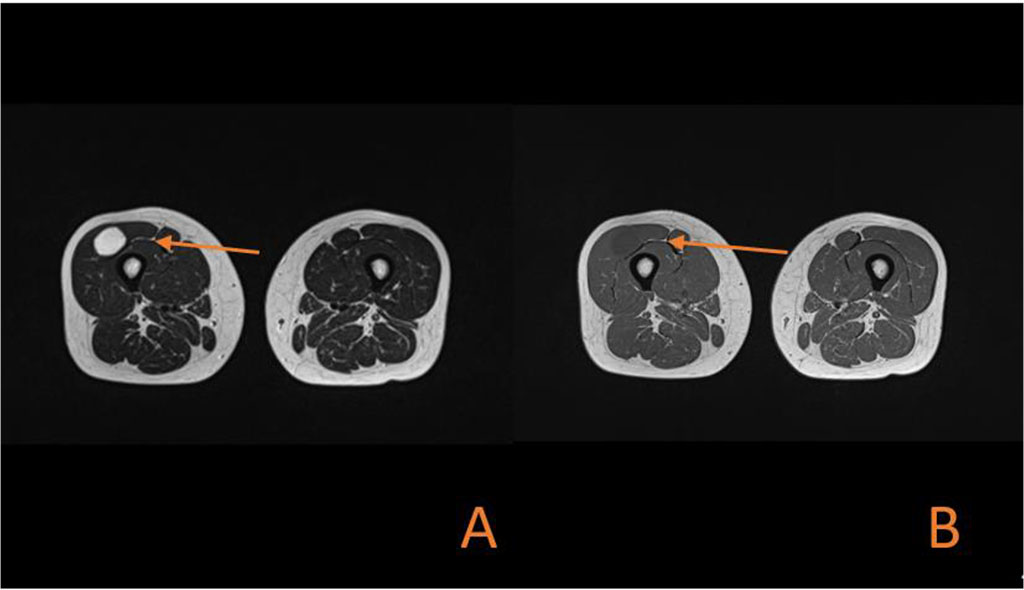

The patient came with laboratory tests and ultrasound results which were performed some time earlier. Laboratory investigation, including a complete blood count, prothrombin time C-reactive protein test showed no abnormalities. Ultrasound examination revealed a well-defined, oval-shaped area of reduced echo intensity within the muscle tissue. Further, more detailed imaging was planned. Magnetic resonance imaging (MRI) confirmed the presence of the tumor. The tumor measured about 6 cm in length, 2 cm in width, and 2 cm in sagittal diameter. It appeared hyperintense on T2-weighted images (Figure 2A, Figure 3A) and hypointense (resembling fluid) on T1-weighted images (Figure 2B, Figure 3B).

Figure 3. (A) Axial MRI section showing high signal intensity on T2-weighted imaging in oval-shaped lesion in the Vastus lateralis. (B) Axial MRI section showing low signal intensity on T1-weighted imaging in oval-shaped lesion in the Vastus lateralis.